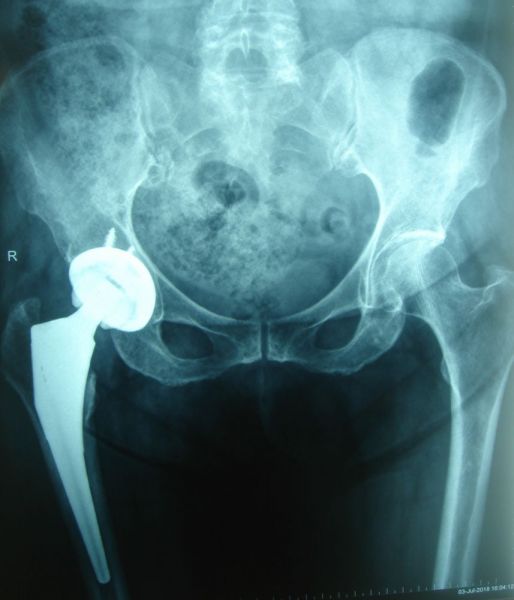

1. Osteoarthritis of both hips but is more severe on the right side.

Treatment: Total hip arthroplasty in a 73-year-old female

I. Anteroposterior x-ray of the pelvis and hips II. One-month post-surgery, anteroposterior x-ray pelvis shows the THA III. One-month post-surgery, lateral x-ray of the right hip showing the exact position of the stem in the femur